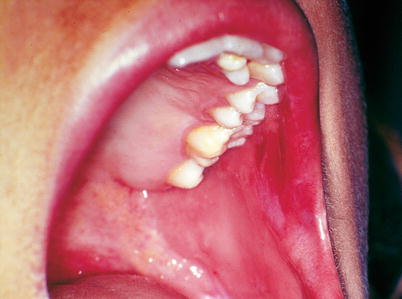

Fig. 2.42

Patient with secondary syphilis, presenting an elevated irregular white necrotic plate with a wrinkled surface located on the on the left side of the edge and belly of the tongue. This condition is known as flat condyloma or papular syphilide. At the top of the image an irregular red plate can be observed covering the hard palate close to the molar teeth